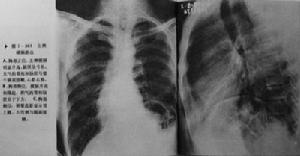

膈膨出檢查診斷:根據臨床表現,輔助檢查如X線檢查可見患側膈肌升高,可升到第三、四前肋間隙高度,膈下緊貼胃泡,膈肌厚度明顯變薄,胸透可見患側膈肌活動受限或消失,有時可見矛盾運動,尤其是後天性膈膨出者更為明顯。

其他輔助檢查:膈膨出主要靠X線檢查作出診斷,胸部X線檢查可見患側膈肌升高,可升到第三、四前肋間隙高度,膈下緊貼胃泡,膈肌厚度明顯變薄,胸透可見患側膈肌活動受限或消失,有時可見矛盾運動,尤其是後天性膈膨出者更為明顯。心臟可向健側移位,並可隨首呼吸發生輕度來回擺動,即在吸氣時擺向健側,呼氣時又返向患側。左側膈膨出時有

膈膨出的病人可因胃體隨上升的膈肌上行而發生胃扭轉,由於胃體部翻轉到胃底上方,胃大彎緊貼於升高的模膈下方,其曲度延長,小彎顯著縮短,胃底倒置,膈下的胃泡氣影則上升到胃體部,在直立前後位檢查時胃底與胃體影重疊,可顯示兩個液平面,在右前斜位形成兩個囊袋,呈倒置“U”字形,在側位檢查時,兩個液平面在前方者屬於幽門竇,在後方者側位於胃底內。